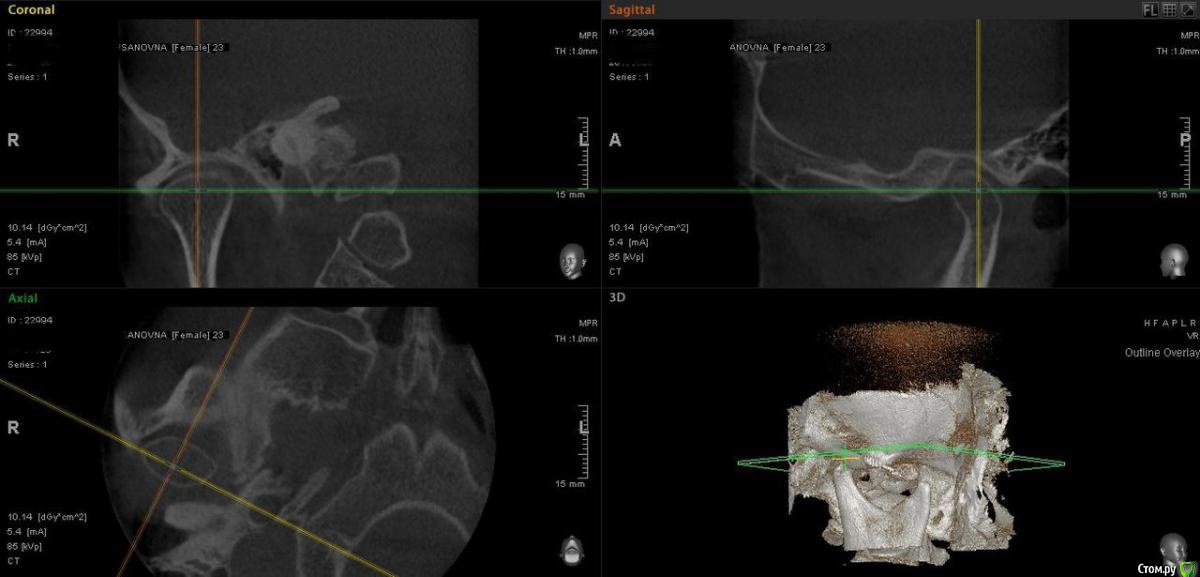

Айсылу Опубликовано 23 июля, 2015 Автор Поделиться Опубликовано 23 июля, 2015 Здравствуйте. Снова я с вопросом к Вам, уважаемые, ортодонты. Вот сделала такие снимки. Ортодонт из "Большого города" сказал, что суставные головки на месте и что выдвигать нижнюю челюсть нельзя. Расширять НЧ уже поздно, из-за возраста. Три варианта решения проблемы мне предложили.:1. Удалить 4-ки (предупредил, что удаление приведет к деформации черепа);2. Хирургическим путем (на этот метод я никогда не решусь);3. снять брекеты. Я записалась на снятие. Для успокоения души решила еще и Ваше мнение узнать... Единственное меня беспокоит тот момент, на сколько губителен этот мой новый дистальный прикус. И что хуже, глубокий прикус, который был до лечения, или же этот, который возник у меня процессе лечения.? Ссылка на комментарий

Айсылу Опубликовано 23 июля, 2015 Автор Поделиться Опубликовано 23 июля, 2015 как Вы себе это представляете? Доктора, которые Вам отвечали и давали свои рекомендации (не снимать, выдвигать НЧ вперед...) сейчас откажутся от своих слов и напишут - снимайте. ? Вам уже давали совет ооооочень грамотные специалисты (это я про Алексей Олеговича и Алексея Сергеевича) Вы приняли другое решение.Неправильный прикус остался. Но многие живут так всю жизнь))) Решение всегда остается за Вам что-то я совсем запуталась...))) я послушалась рекомендаций.обратилась к более опытному ортодонту из близлежащего Большого города. Он рекомендовал мне пройти дополнительное обследование. по результатам снимков моего сустава он сделал такие выводы. До этих снимков он тоже хотел выполнить репозицию нижней челюсти. Но в результате он сказал то, что я написала выше. Я вот именно что не хочу снимать, пока результата полного не будет. Пишу я удостоверится действительно ли мне правильно сказали все выходы из моей ситуации. P/S я ведь еще не сняла брекеты))) Ссылка на комментарий